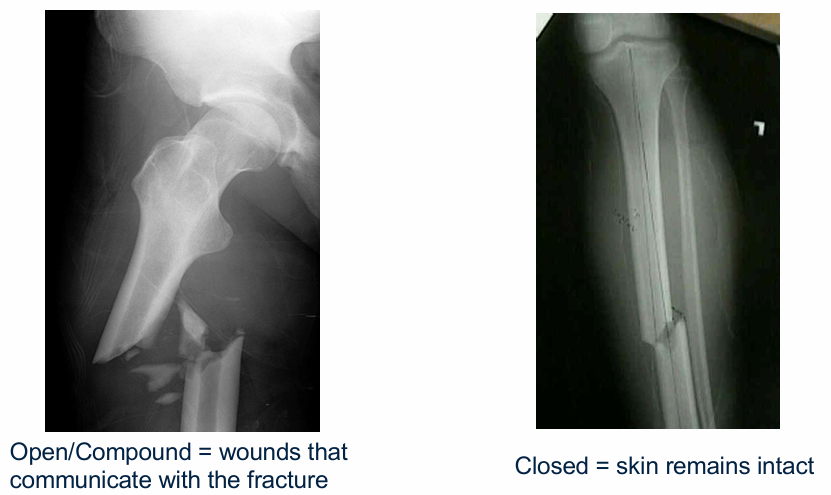

What is the difference between open and closed fractures?

Open fractures communicate with the external environment (e.g. femur poking through the skin)